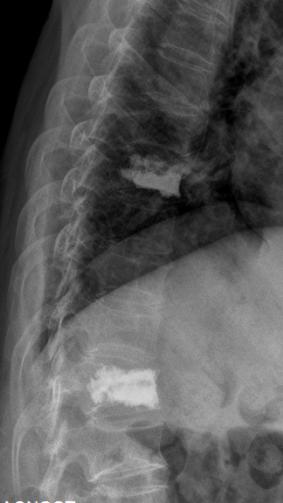

术前核磁共振检查明确T8.12椎体骨折,为疼痛责任椎体;经皮穿刺微创椎体成形术后复查可见椎体高度恢复良好,骨水泥弥散满意。

术前过伸位X、CT检查,早期诊断